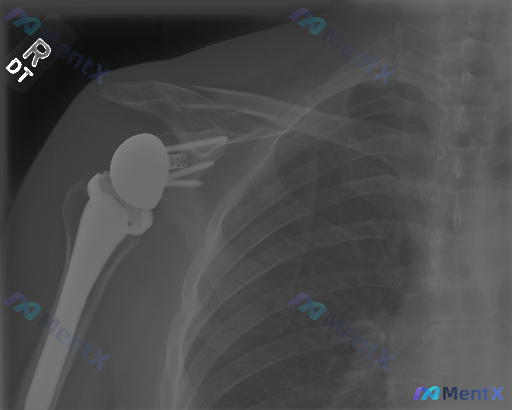

整理了一份右肩关节置换术后的影像学分析资料,先把核心影像表现放出来,看看大家第一眼的读片思路会怎么走。 影像核心所见(仅基于这份单时点X光): - 可见右肩关节假体(肱骨侧柄+球头、关节盂侧底座+螺钉),位置在位 - 假体-骨界面贴合紧密,未见明显透亮线(松动征象) - 关节对位正常,无半脱位/移位...

整理到一份肩关节的影像病例,有点意思: 基础情况: - 右侧肩关节置换术后复查X光(正位) 影像科给出的显性结论: 1. 假体位置良好,无明显脱位/半脱位 2. 假体周围无明确骨折线,骨皮质连续 3. 无明显透亮带(>2mm)、骨溶解或恶性征象 4. 肩周软组织无明显钙化或广泛肿胀 但这里有个冲突点...